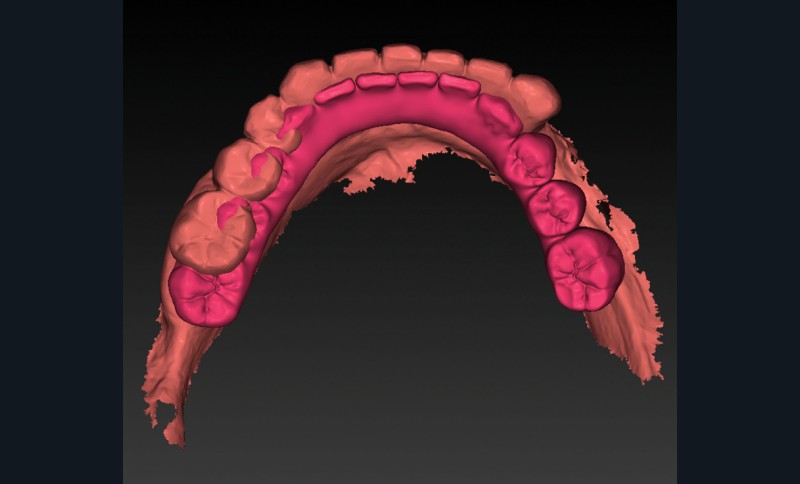

- les empreintes (fig. 3) transmises au laboratoire pour la réalisation d’un wax-up digital (fig. 4) préfigurant la position idéale des dents prothétiques. Ce modèle prothétique virtuel permet de déterminer la position, l’axe et la profondeur idéale des implants en fonction du couloir osseux, des tissus mous et du positionnement souhaité des puits de vissage.